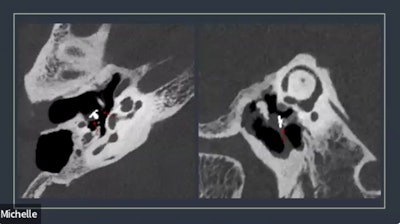

"We had a policy that you had to convince the group," he said, noting examples where the group saw evidence that diagnostic imaging using PCCT improved patient management and outcome in cases involving temporal bone imaging (highlighting an eroding ossicular implant), and pediatric cystic fibrosis.

"Those are both diagnoses that were only able to be made on this scanner that could not be made when the patient was scanned on the conventional force scanner," Froemming said, noting "huge dose reduction potential, and much more actionable clinical information."

Temporal bone imaging using photon counting CT illuminated the ossicular implant.Adam Froemming, MD, Mayo Clinic, via ISCT.